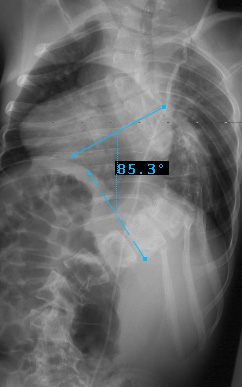

Preop LEFT Bend

Preop RIGHT Bend